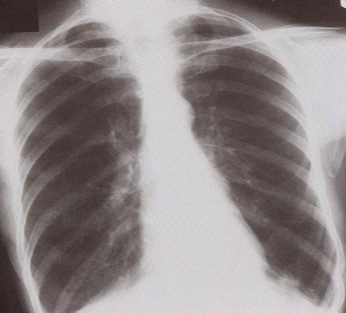

What features are seen on this CXR? What is the likely diagnosis?

hyperexpanded + flattened diaphragm

COPD